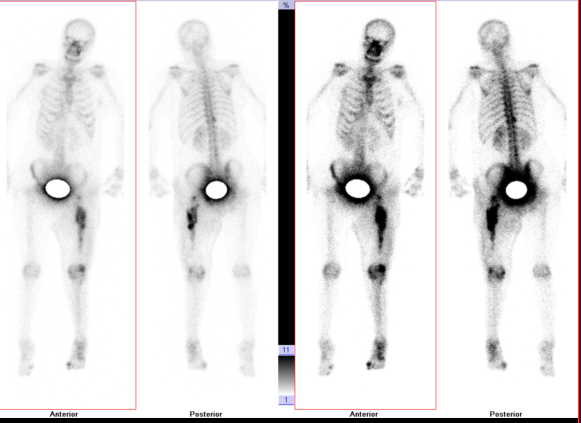

第一例患者女性,48岁,因“左大腿疼痛2月余,疼痛突然加重伴肿胀、畸形、活动障碍5天”入院。查体见痛苦病容,左大腿上端明显肿胀,呈屈曲、外旋、短缩畸形,左大腿中上段压痛明显,皮温升高,可触及骨擦感,左下肢活动障碍。初步诊断为左股骨病理性骨折。左股骨X线提示:左侧股骨近端虫蚀样骨质破坏并骨折,局部软组织密度改变。CT提示:左侧股骨上端广泛虫蚀状骨质破坏,中上段为著,周围软组织肿胀,考虑左侧股骨恶性骨肿瘤并病理性骨折。全身骨显像:左侧股骨中上段代谢异常增高伴软组织肿块,结合MRI考虑恶性骨肿瘤继发病理性骨折。后行穿刺活检,病理提示:符合转移性肺腺癌;(左侧远端髓腔肿物)见腺癌组织。由于患者非常痛苦,后并发下肢静脉血栓,其家属强烈要求手术,经我院医护对其全身严格评估并妥善处理下肢静脉血栓后,术前多学科讨论认为符合手术适应症,遂顺利行瘤段切除,人工假体置换重建术,髋关节囊及股骨上端重要肌肉附着点均使用laser韧带重建,历时3小时余。术后患者剧痛、烦躁、失眠等症状消失,活动明显增加,护理方便,医患双方对疗效非常满意,为后续治疗创造了有利条件。

全身扫描ECT图

第二例患者男性,76岁,因“右大腿剧烈疼痛伴烦躁失眠,活动明显受限40余天”入院。查体见:痛苦病容,右大腿上端略肿胀,局部皮温略高,可触及包块,扣压痛明显,有骨擦音及异常活动,叩击足底时右大腿根部剧烈疼痛,余无明显异常。初步诊断为右股骨恶性肿瘤并病理性骨折。入院检查右股骨X线提示:右侧股骨近端虫蚀样骨质破,局部软组织密度改变。胸部CT平扫:1.双肺间质性改变,左肺上叶空洞型病变,邻近多发小结节及条索影,结核多考虑,请结合临床。 2.甲状腺多发钙化灶及小结节。 3.SPECT全身骨显像:右侧股骨近端代谢增高与减低并存,骨肿瘤与骨结核待进一别。穿刺活检病理提示为:(股骨)转移性腺癌。全身检查,未发现原发灶。该患者疼痛症状剧烈,伴烦躁不安,昼夜不眠,食欲不振,非常痛苦,服药效果不佳,曾要求截肢。其家属也强烈要求手术,全身严格评估后,术前多学科讨论认为符合手术适应症,遂顺利行瘤段切除,人工假体置换重建术,历时3小时半。术后患者以上不良症状均明显缓解,患者感激涕零,活动明显增加,三天后扶拐下地,医患双方对疗效非常满意,准备两至三周后行化疗及支持治疗。